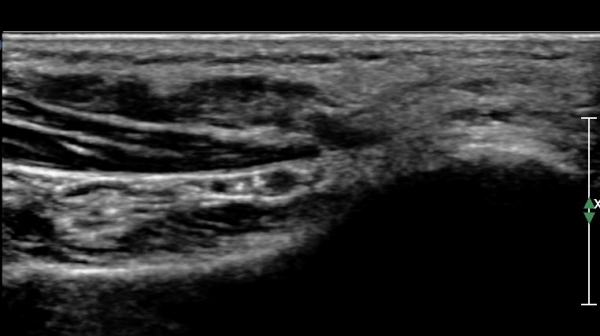

ŽÃËÀÚ¸¦ Á¶±Ý ´õ ¹ß¹Ù´ÚÃøÀ¸·Î À̵¿ÇÏ´Ï ¾Æ·¡µÚ²ÞÄ¡½Å°æÀÌ Àú¿¡ÄÚ µ¢¾î¸® ¸ð¾çÀ¸·Î °üÂûµÈ´Ù

(»çÁø 3, 4)